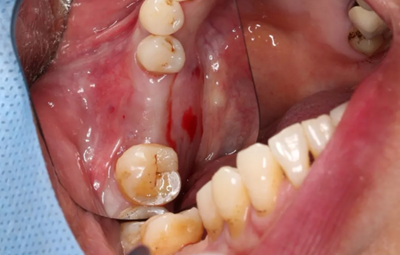

取下攜帶體,旋入封閉螺絲,潛入式愈合。

(攝于2017年4月14日)

組織瓣復(fù)位,常規(guī)間斷縫合。